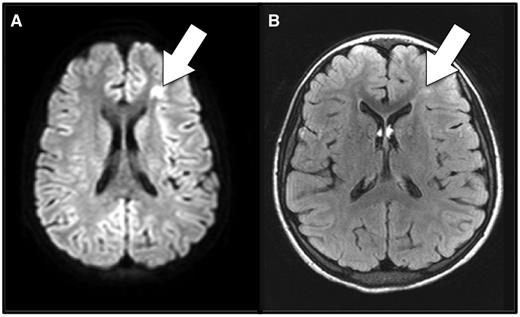

Anemia and cerebral ischemia. Shown here is magnetic resonance imaging of the brain during (A) and 7 months after (B) an acute anemic event in a patient with sickle cell anemia who had no focal neurologic signs corresponding to the brain lesion. A focus of restricted diffusion on diffusion-weighted imaging (A) indicates this is an acutely ischemic lesion. (B) Typical, T2-hyperintense, permanent silent cerebral infarct corresponding to the focus of the acute ischemia detected during the acute anemic event. The imaging was obtained for a screening clinical research study, not for clinical suspicion of stroke.

Three reports have shown that SCIs are detectable during the acutely ischemic phase (see figure). The first was a case series of 7 patients who had “acute SCI” or acute silent cerebral ischemic events (ASCIEs) during complications of SCA, 4 of which were AAEs.5 A prospective study showed that ASCIEs occurred in nearly 20% of children with SCA hospitalized for AAEs, defined as a Hb level of <5.5 g/dL and 30% or more lower than baseline.6 A multicenter study showed that ASCIEs could also be detected in asymptomatic, clinically well children undergoing screening magnetic resonance imaging of the brain.7 Compared with the baseline rate of initial SCIs, the rate of ASCIEs was 40-fold higher in children who already had a “remote” SCI, whereas AAE increased the incidence of ASCIEs 600-fold.6-8 Some ASCIEs appear to be reversible and leave no detectable lesion, whereas others become permanent SCIs.